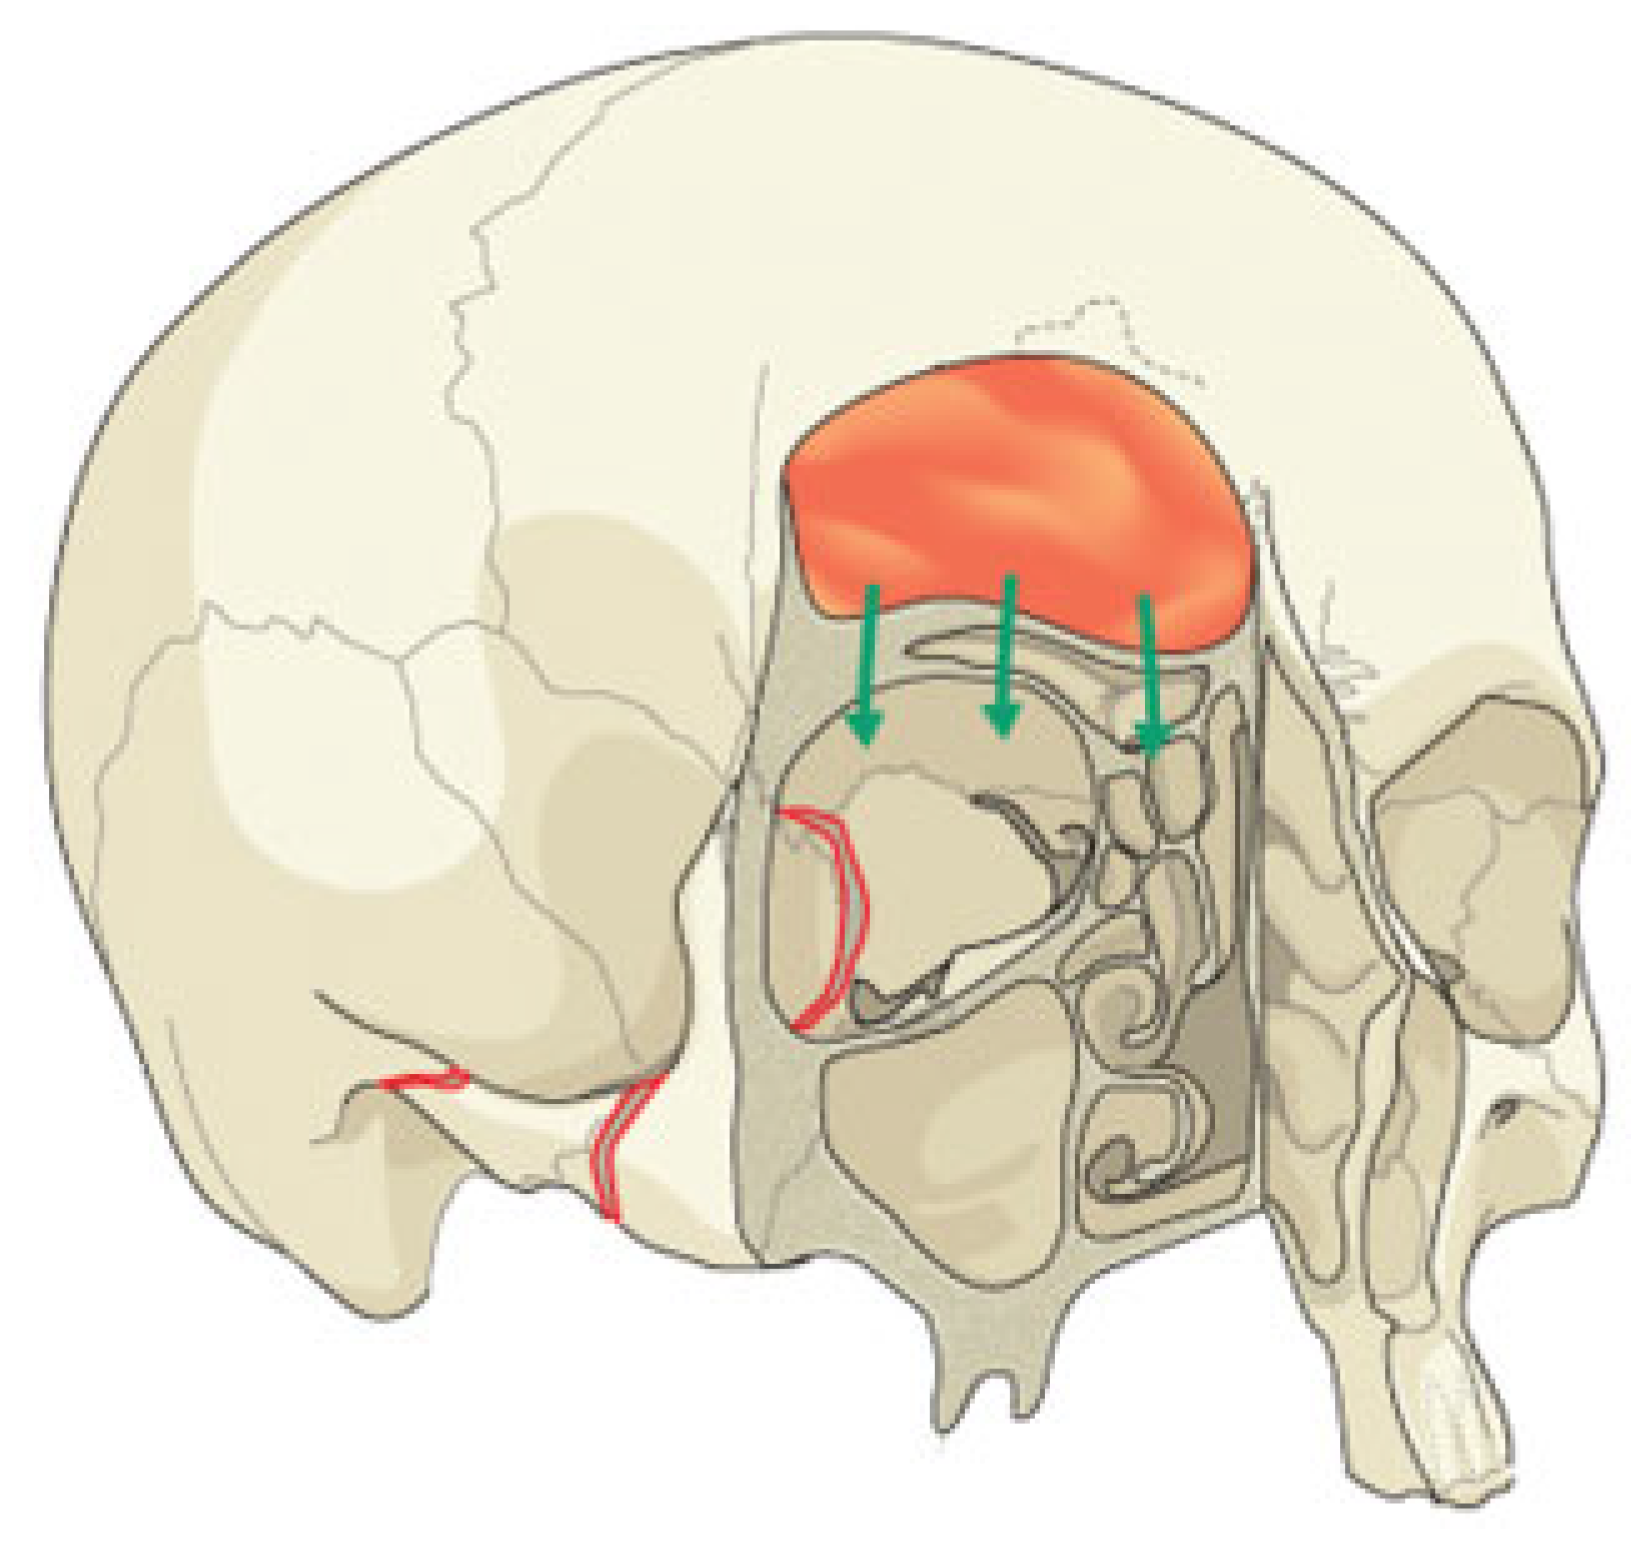

Figure 9. The growing skull fracture. When a dural tear occurs beneath a displaced orbital roof fracture, a leptomeningeal cyst may form during the regenerative process. The cyst interferes with osseous healing, and frontal bone nonunion results. Pulsatile exophthalmos ensues, due to compression (arrows) of the orbital cavity.

In children, the most common fracture pattern extends along the frontal bone through the supraorbital foramen, and then progresses to involve the orbital roof/anterior cranial base [47]. Generally these craniofacial fractures do not require open reduction and internal fixation (ORIF) unless a significant displacement is observed. In such cases, a so-called “growing skull fracture” may occur. The growing skull fracture is a unique entity among pediatric orbital fractures [48]. John Howship, an English surgeon, first reported this condition 1816 as “partial absorption of the (right) parietal bone, arising from a blow on the head” [49]. When a dural tear occurs beneath a displaced orbital roof fracture, a leptomeningeal cyst may form during the regenerative process. The cyst interferes with osseous healing, and frontal bone nonunion results (Figure 9). Pulsatile exophthalmos ensues, due to compression of the orbital cavity. Vertical ocular dystopia results, and vision is threatened from orbital compartment syndrome and optic nerve compression [50]. The treatment of growing skull fractures involves a transcranial approach. Excision of the leptomeningeal cyst is followed by reconstruction of the dural and bony defects [51,52]. Split calvarial bone grafting is required for the latter defect, and resorbable plates and screws are used to secure the graft.